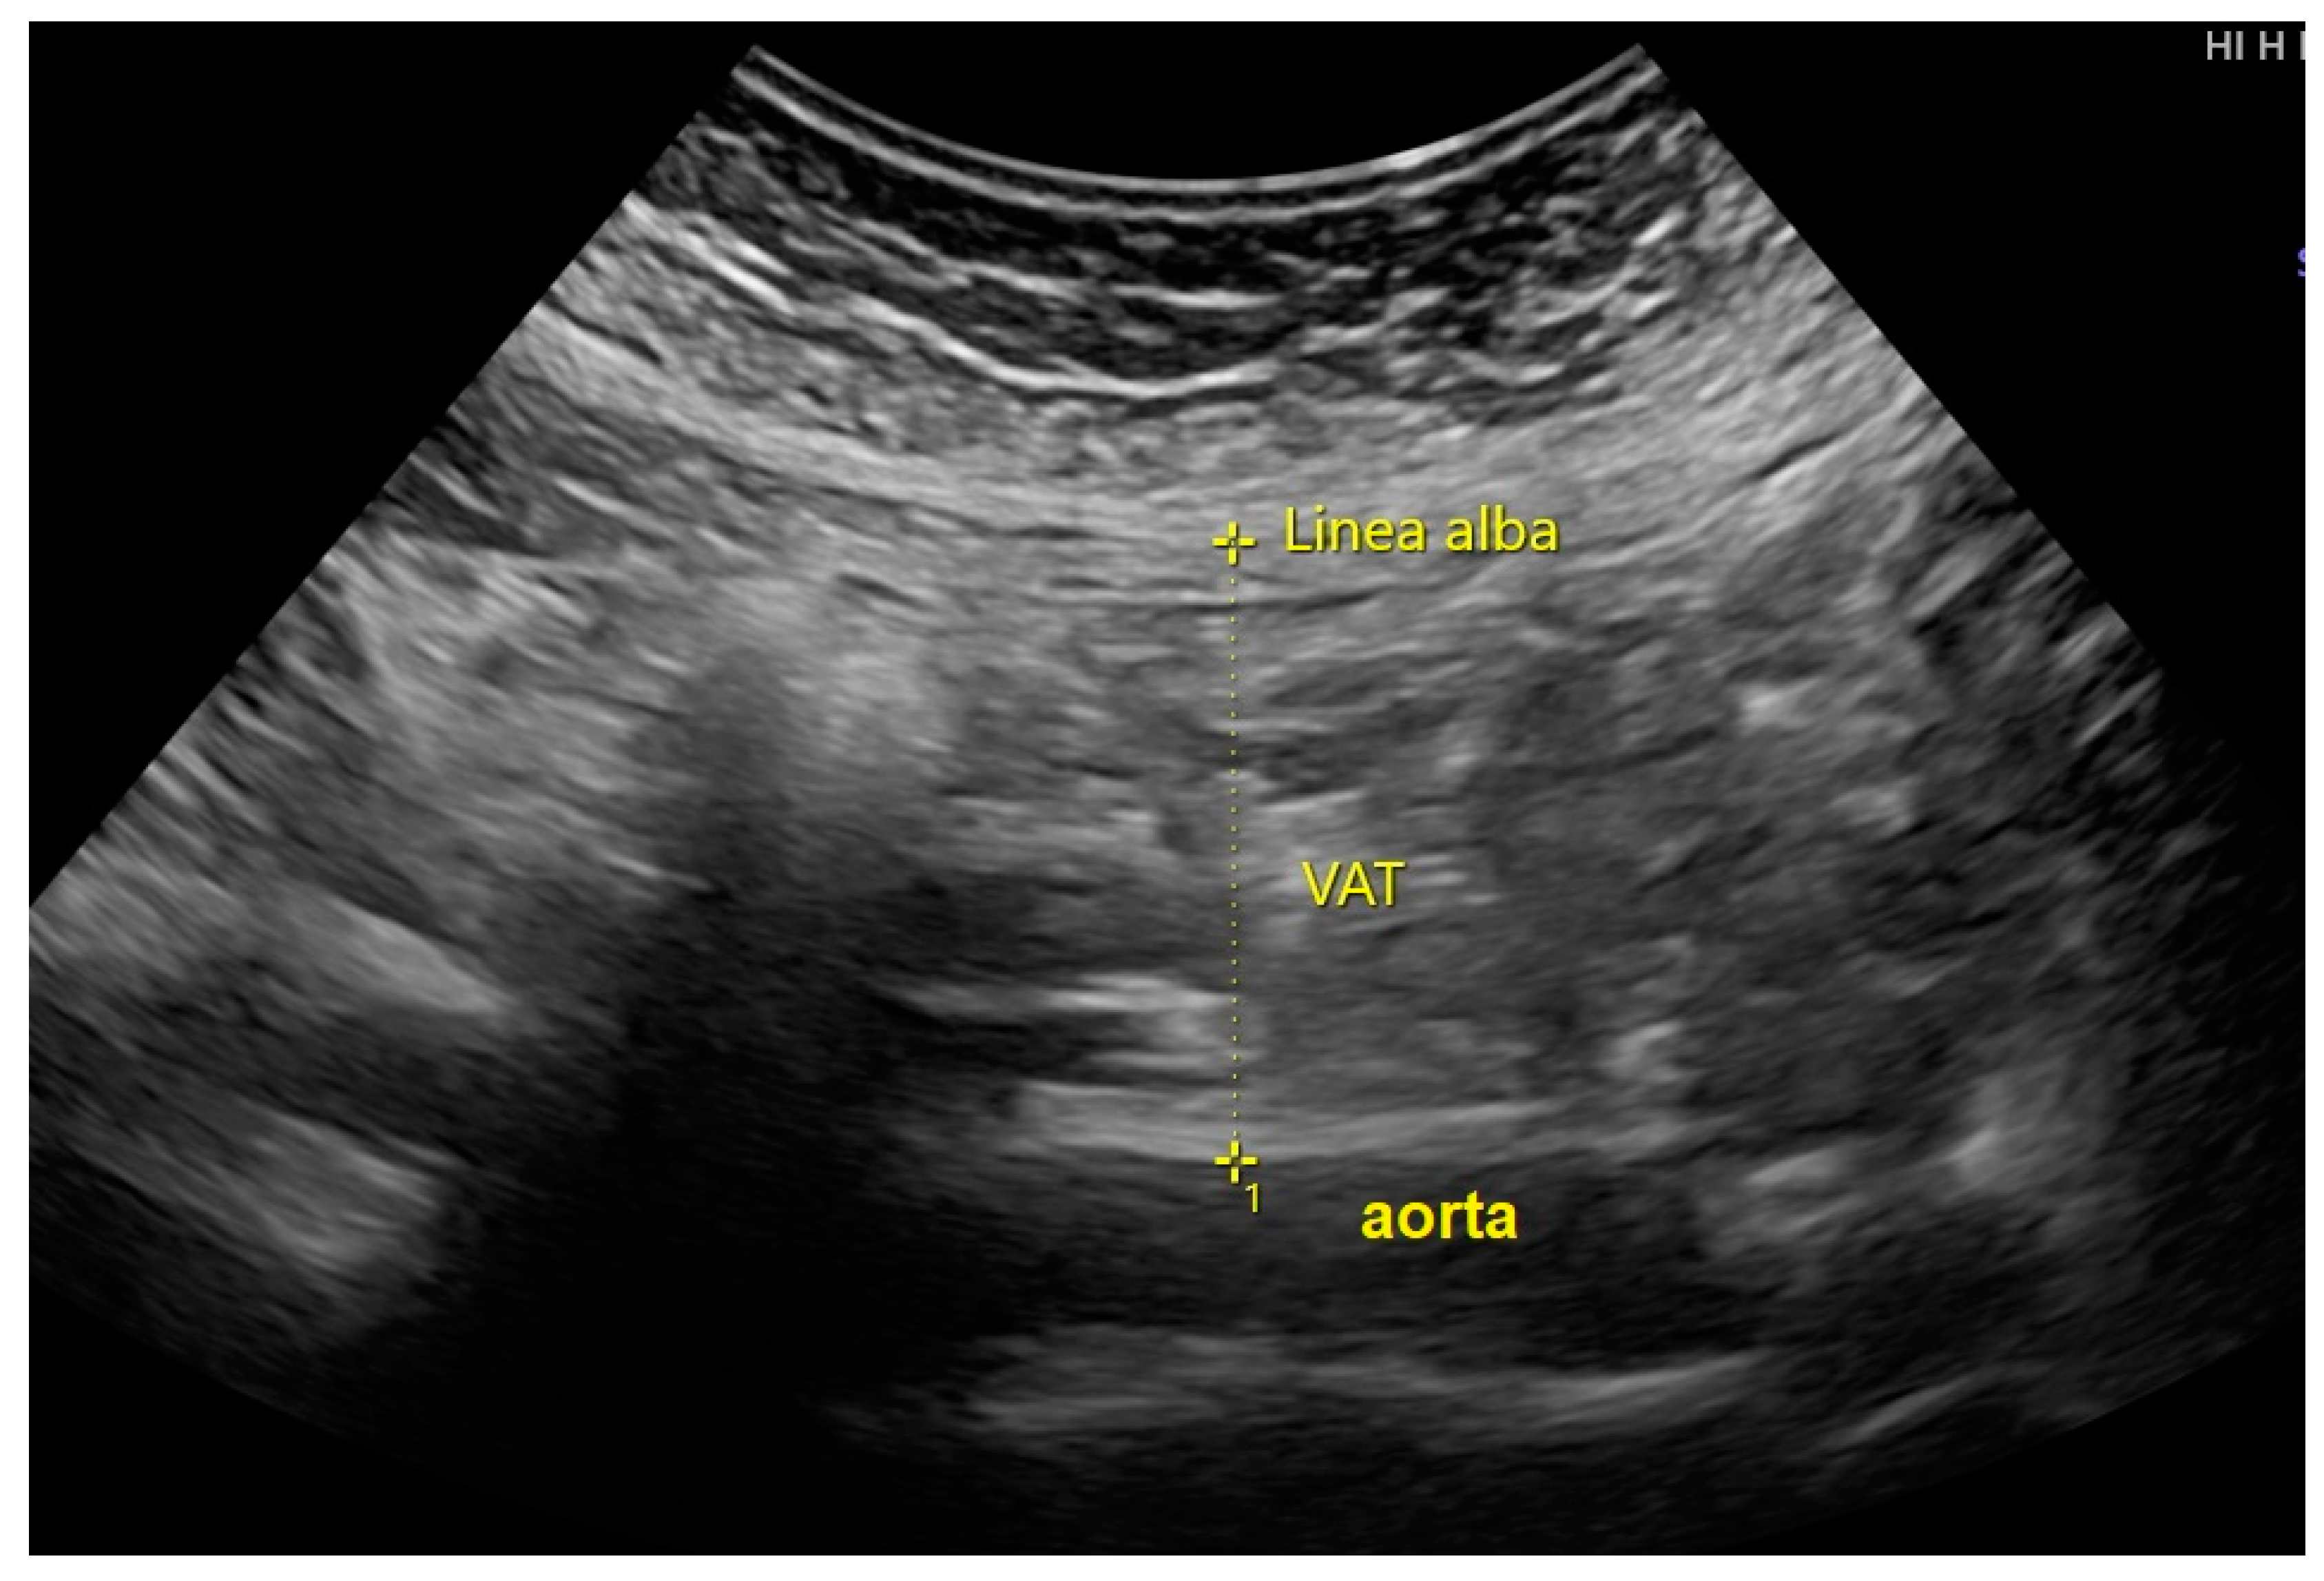

2. Patients and Methods